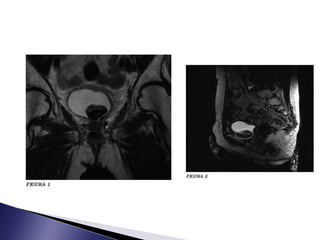

RM

 Alternativa aUIV en pacientes con IRC  Se visualiza el trayecto afectado dilatado que maneja 10UH y hasta 30UH en pionefrosis  Visualiza litiasis y el tejido periureteral  Discrimina si la obstrucción es intrínseca o extrínseca